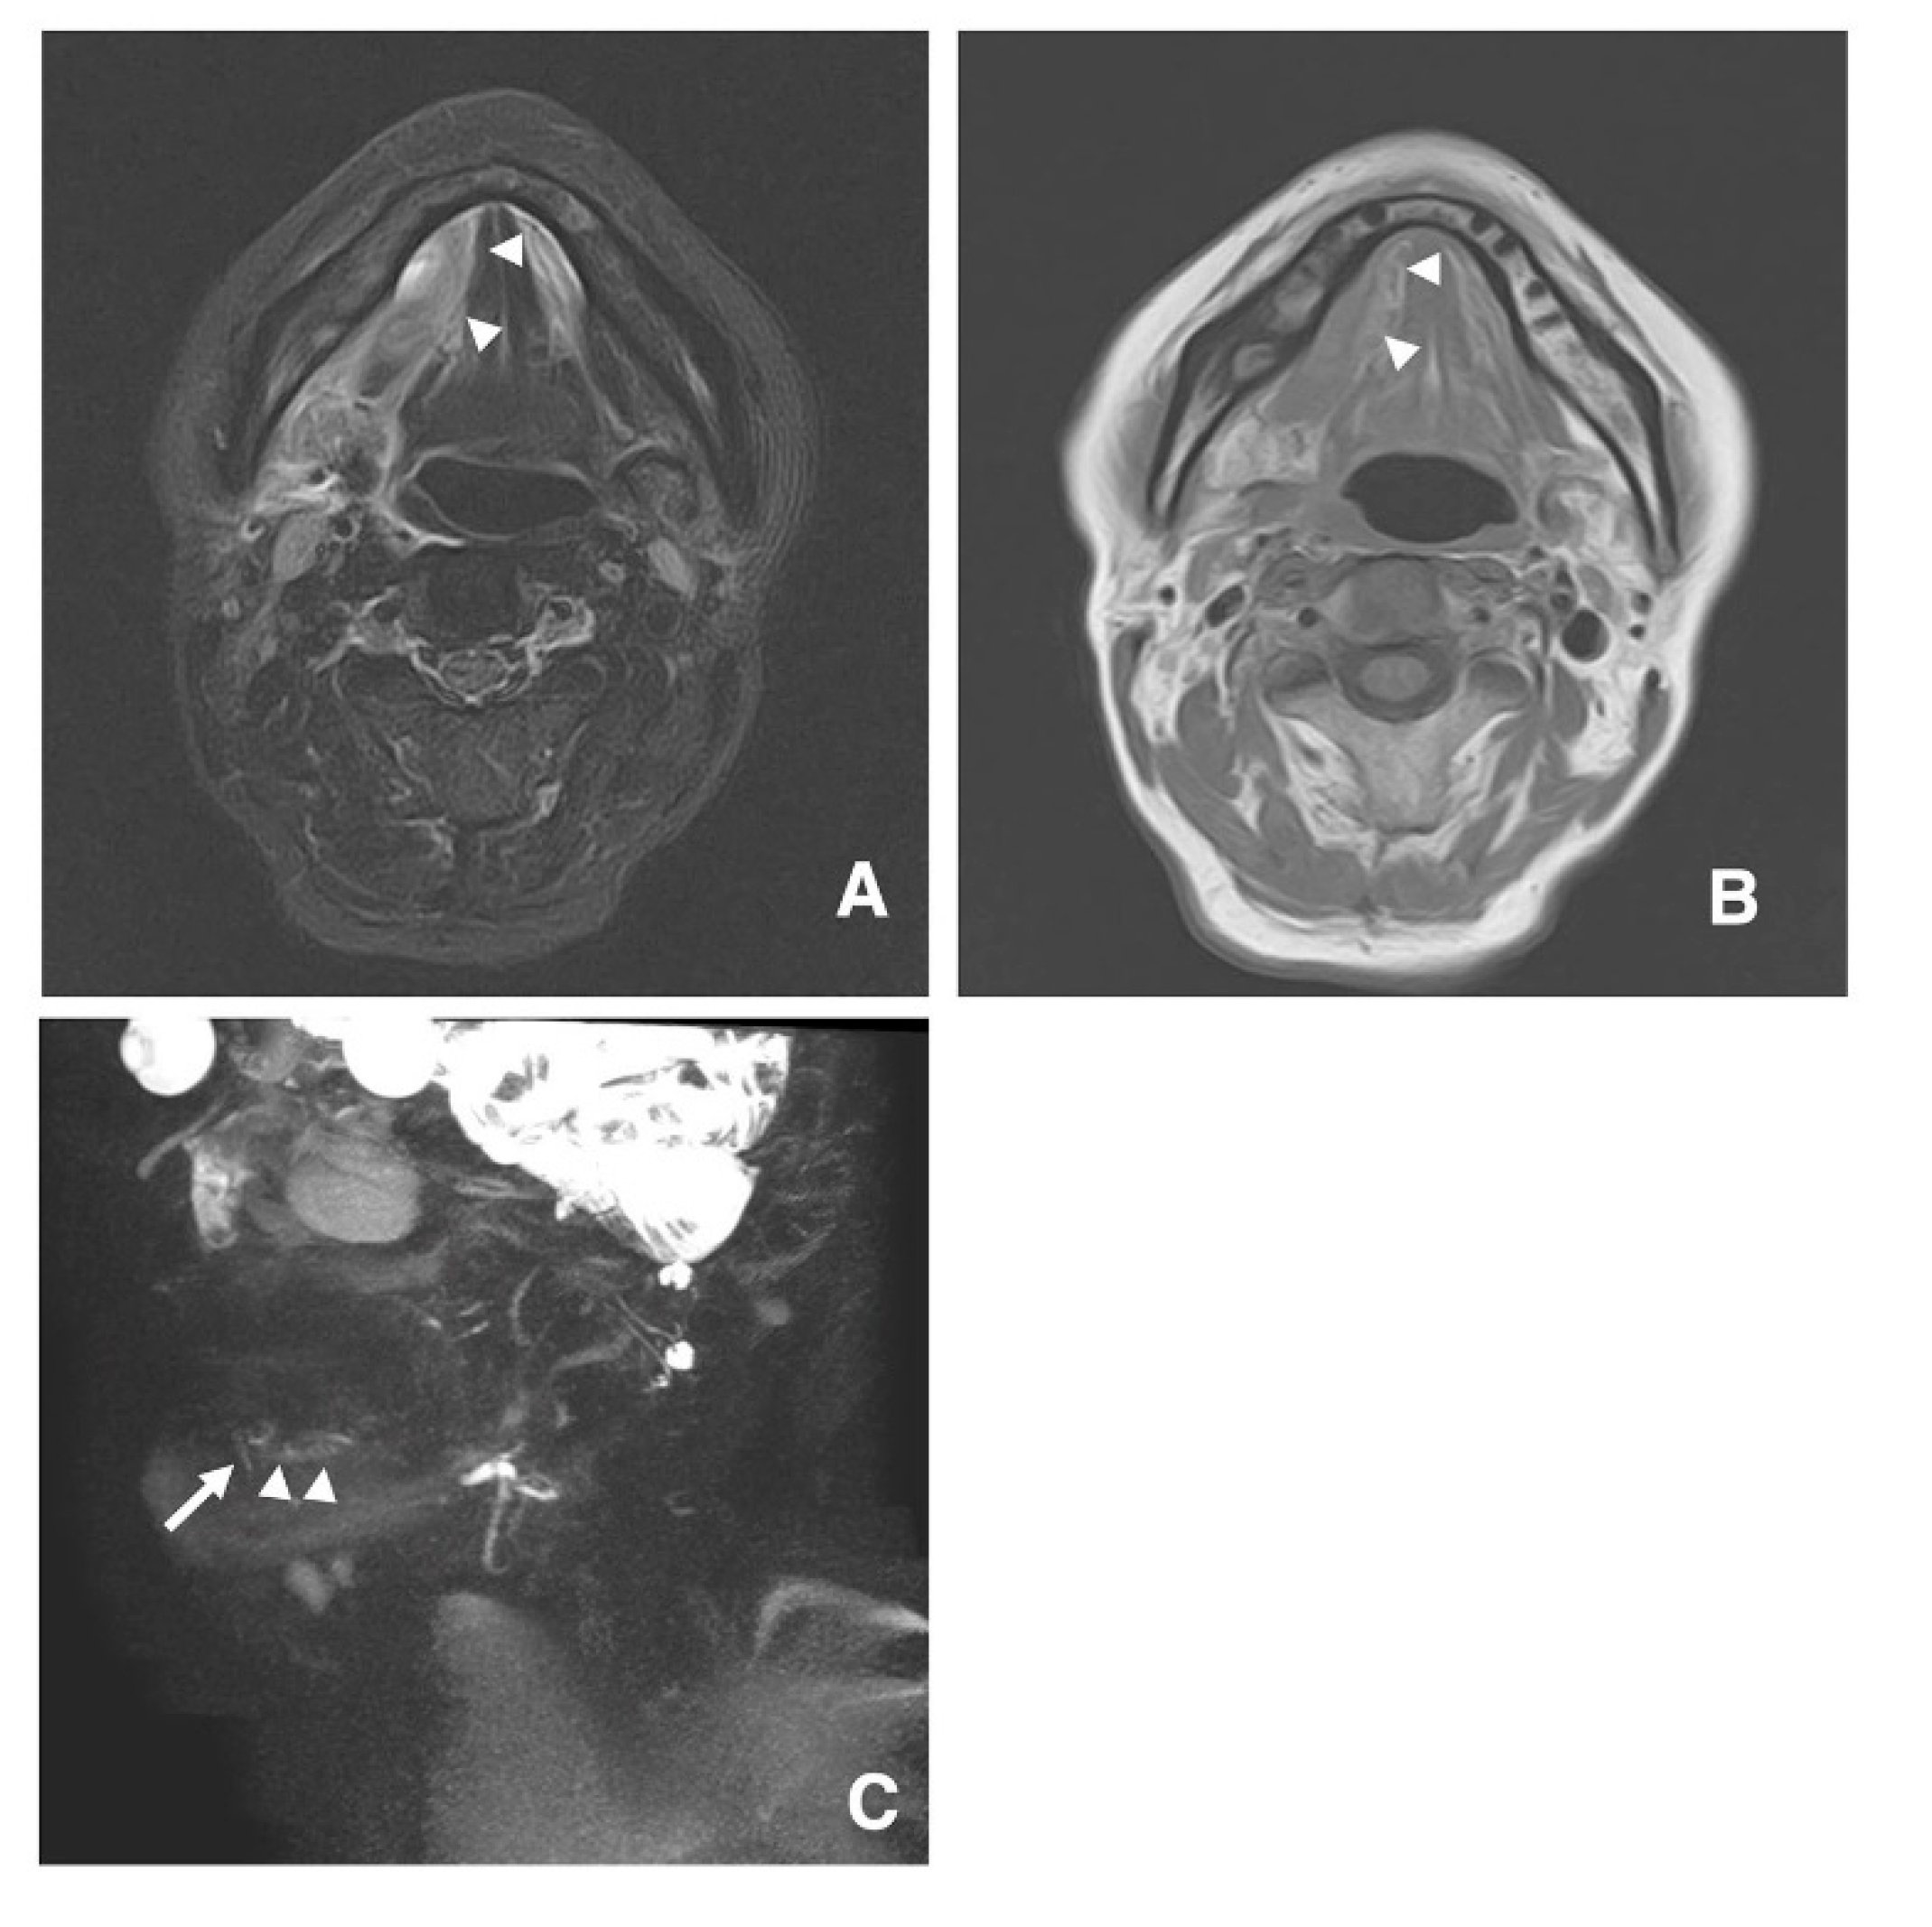

3.3. Clinical Application of MR Sialography for Patients with Sublingual Gland Diseases